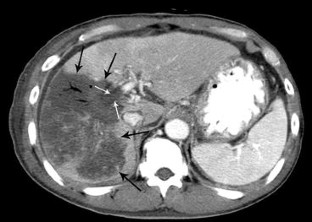

FIG. 1